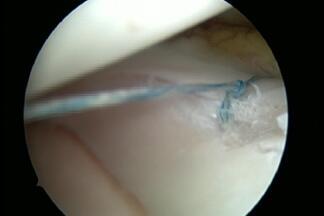

The inner and outer meniscus serve to buffer the load and stabilise the joint. Damage to the meniscus can occur due to accidents, or wear and tear, or a combination of both. The consequences are pain, swelling, and possibly also entrapment. Meniscus damage occurs most frequently between the ages of 30 and 50. Men are affected twice as often as women (9 to 4.2/10000 respectively). If the damage is symptomatic, it can be repaired minimally-invasively by arthroscopy. The follow-up treatment depends on whether parts of the meniscus were removed (pain-adapted full weight-bearing) or whether the meniscus was sutured (usually partial weight-bearing). Unfortunately, only a few meniscus tears are suitable for suturing.